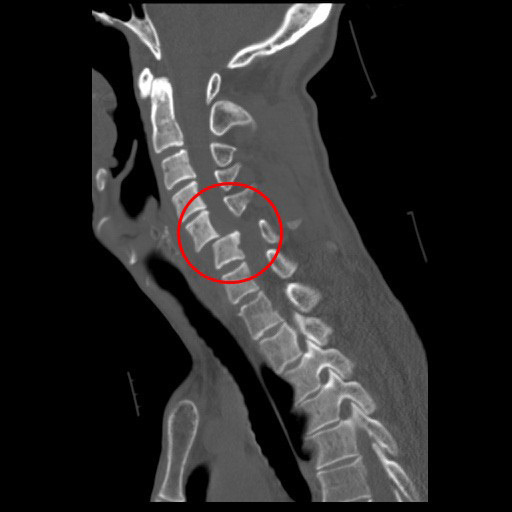

「當時身體沒有其他外傷,但雙手就是不聽使喚,無法動彈!」在轎車中受到劇烈撞擊的宋先生,只覺得頸椎劇痛。正逢休假期間的神經脊椎微創外科主任洪祥益一收到通知,就趕回醫院緊急為宋先生進行手術,洪祥益主任表示,宋先生的頸椎第五、六節骨折脫臼,如同竹子斷成兩截,其中脊髓神經受到擠壓幾乎快斷,所以導致雙手癱瘓。

洪祥益主任五個小時內為宋先生進行三階段手術,一是先將頸椎骨折脫臼復位,接下來以顯微鏡清除壓迫到神經的破碎椎間盤和骨刺後再融合,最後在頸椎後方以四根釘子做後固定加強,等於頸椎前後做了三百六十度的固定融合手術。